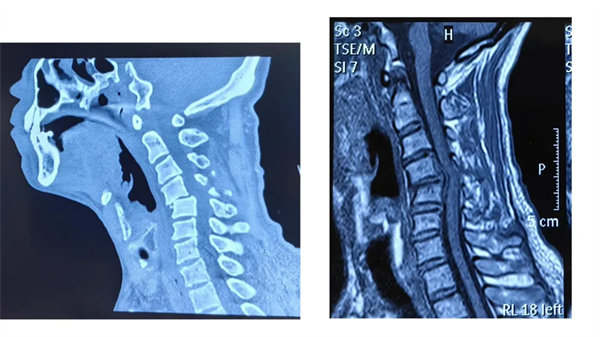

近日,我院骨四科團隊成功為一名因摔傷導致頸4/5椎骨折脫位、頸脊髓損傷的60歲男性患者實施前路切開復位椎間盤切除減壓植骨椎間融合術(ACDF),幫助患者擺脫病痛,重新回歸正常生活。這一病例也為公眾敲響警鐘:看似常見的頸椎損傷,若處理不當可能引發(fā)嚴重后果,科學救治刻不容緩。

患者受傷后曾在外院接受保守治療,但肢體麻木癥狀持續(xù)存在。轉入我院時,頸椎CT及MRI顯示:頸4/5椎骨折脫位,脊髓受壓明顯,若不手術治療,可能面臨永久性神經功能障礙。我院骨四科團隊,制定了前路ACDF手術方案:通過頸前側入路,切開復位、切除椎間盤,解除脊髓壓迫,同時植入融合器、鈦板固定,重建頸椎正常序列及穩(wěn)定性。術后患者麻木感消失,復查顯示頸椎序列恢復良好,目前已康復出院。